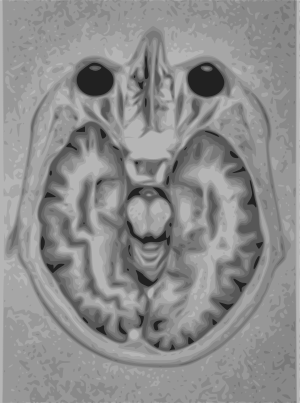

التصوير بالرنين المغناطيسي (MRI)

التصوير بالرنين المغناطيسي يستخدم مغناطيسات قوية ليستقطب نواة الهيدروجين (بروتون وحيد) في جزيئات الماء الموجودة في الأنسجة البشرية مولدة إشارة قابلة للالتقاط حيث يتم فك تشفيرها معطية صورة للجسم. يستخدم التصوير بالرنين المغناطيسي ثلاث أنواع من الحقل الكهرومغناطيسي: حقل مغناطيسي ساكن قوي جداً (من فئة عدة واحدات تسلا) من أجل استقطاب نويات الهيدروجين، يدعى بالحقل الساكن، هناك حقل أضعف منه متغير مع الزمن (من فئة 1 كيلو هرتز) من أجل الترميز الخاص، يسمى بحقل الميلان، وحقل موجات راديوية ضعيف من أجل التلاعب بنويات الهيدروجين لإنتاج إشارات ممكنة القياس يتم تجميعها خلال هوائي الموجات الراديوية. كما في الأشعة المقطعية فإن التصوير بالرنين المغناطيسي انتج صوراً للمقاطع والشرائح الرقيقة للجسم ولذلك تم اعتباره نوعاً من أنواع التصوير بالأشعة المقطعية. تتمكن أجهزة التصوير بالرنين المغناطيسي الحديثة من إنتاج صوراً ثلاثية الأبعاد والتي تعتبر تعميماً للصور الثنائية البعد. على خلاف التصوير بالأشعة السينية فإن التصوير بالرنين المغناطيسي لا يستخدم أي نوع من الأشعة المؤينة وبالتالي فإنه لا يتصاحب مع مخاطر صحية، حيث أنه ليس من المعروف وجود أي مخاطر صحية على المستوى البعيد للتعرض إلى حقل مغناطيسي ساكن قوي ولكن هذا الأمر لا يزال موضع جدال وبحث علمي. ولذلك لا يوجد أي تحديد لعدد المرات التي من الممكن للمريض أن يتعرض لها للتصوير بالرنين المغناطيسي على خلاف التصوير بالأشعة السينية. ولكن يوجد مخاطر صحية من جراء تسخين الأنسجة بتعريضها لحقل الأمواج الراديوية والتأثير على الأجهزة المزروعة ضمن الجسم كمنظمات عمل القلب. على اعتبار أن طريقتي التصوير بالأشعة المقطعية والتصوير بالرنين المغناطيسي تختلفان في حساسيتهما لمواد الأنسجة المختلفة، لذلك فإن الصور الناتجة عن كلا الطريقتين تختلف بشكل ملحوظ. تنتج الصور في الأشعة السينية المقطعية عن طريق حجب مرور الأشعة بواسطة الأنسجة الكثيفة، بينما تكون جودة الصورة ضعيفة في مناطق الأنسجة الطرية. بينما بروتون الهيدروجين يكون موجوداً في معظم الأنسجة الطرية التي تحتوي على الكثير من جزيئات الماء. وهنا تستخدم تقنية مطابقة الصور بواسطة الكمبيوتر للحصول على صورة واضحة لمختلف الأنسجة بمطابقة صورتي الأشعة السينية والرنين المغناطيسي.